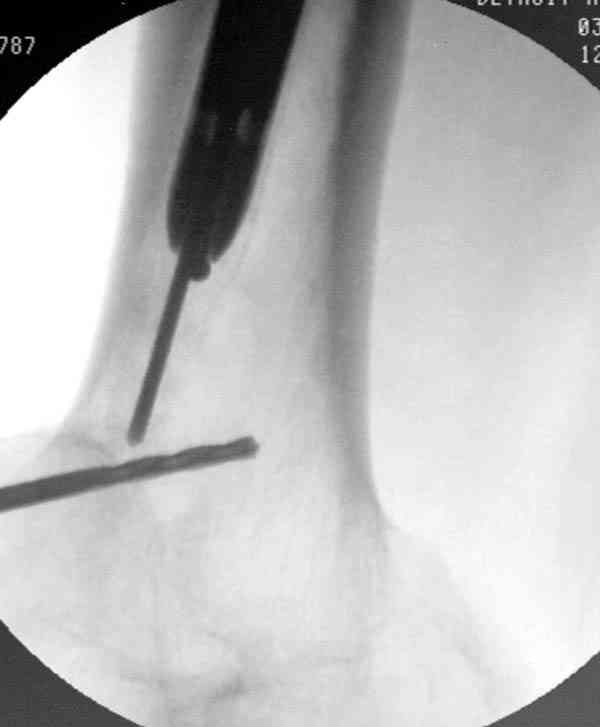

Приспособление для удаления сломанных штифтов и наличие ЭОП облегчит задачу. При отсутствии крючка тогда можно применить обычный длинный ball pointed guide wire от интрамедулярного набора. Проволока, пропущенная за пределы гвоздя и зажатая другая вытащат сломанный конец штифта без проблем.